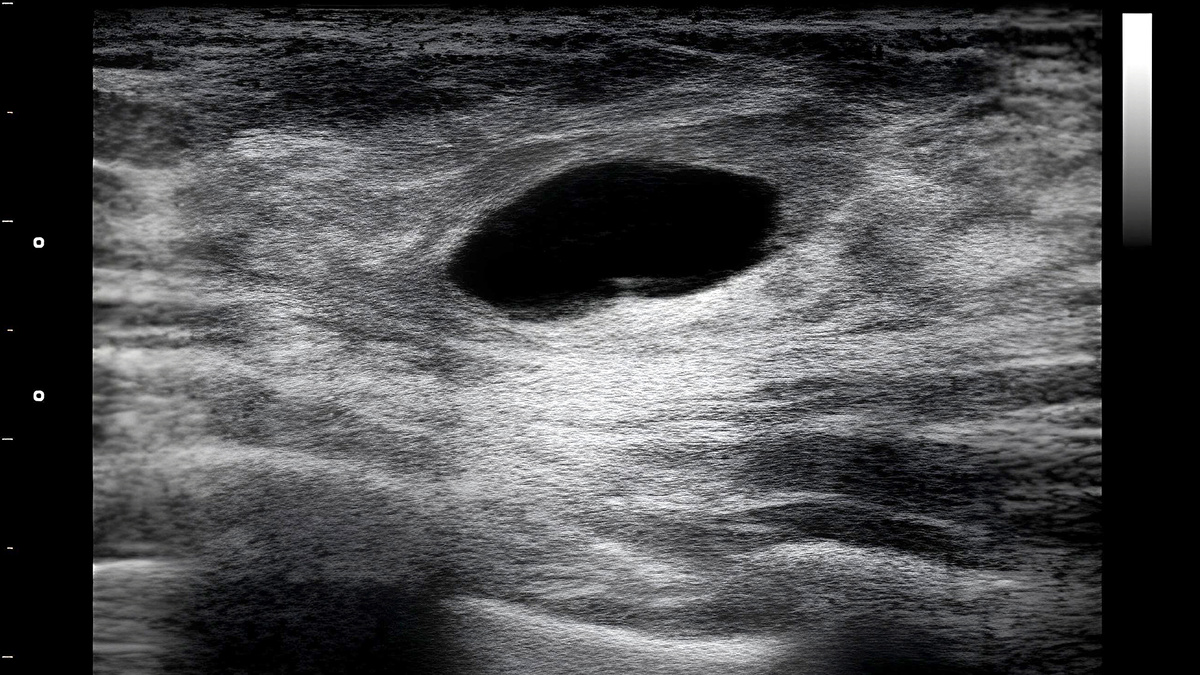

На ультразвуковом исследовании (УЗИ) молочных желез кисты представляются округлыми тонкостенными анэхогенными образованиями с четкими контурами. Это так называемые простые кисты.

Сложные кисты характеризуются толстой стенкой, образованиями внутри кисты, или солидным компонентом в структуре кисты.